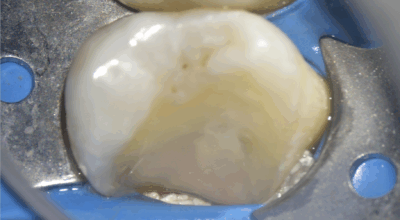

Clinical case of tooth 17 (upper right second molar)

Indirect pulp capping: 96.4% success rate